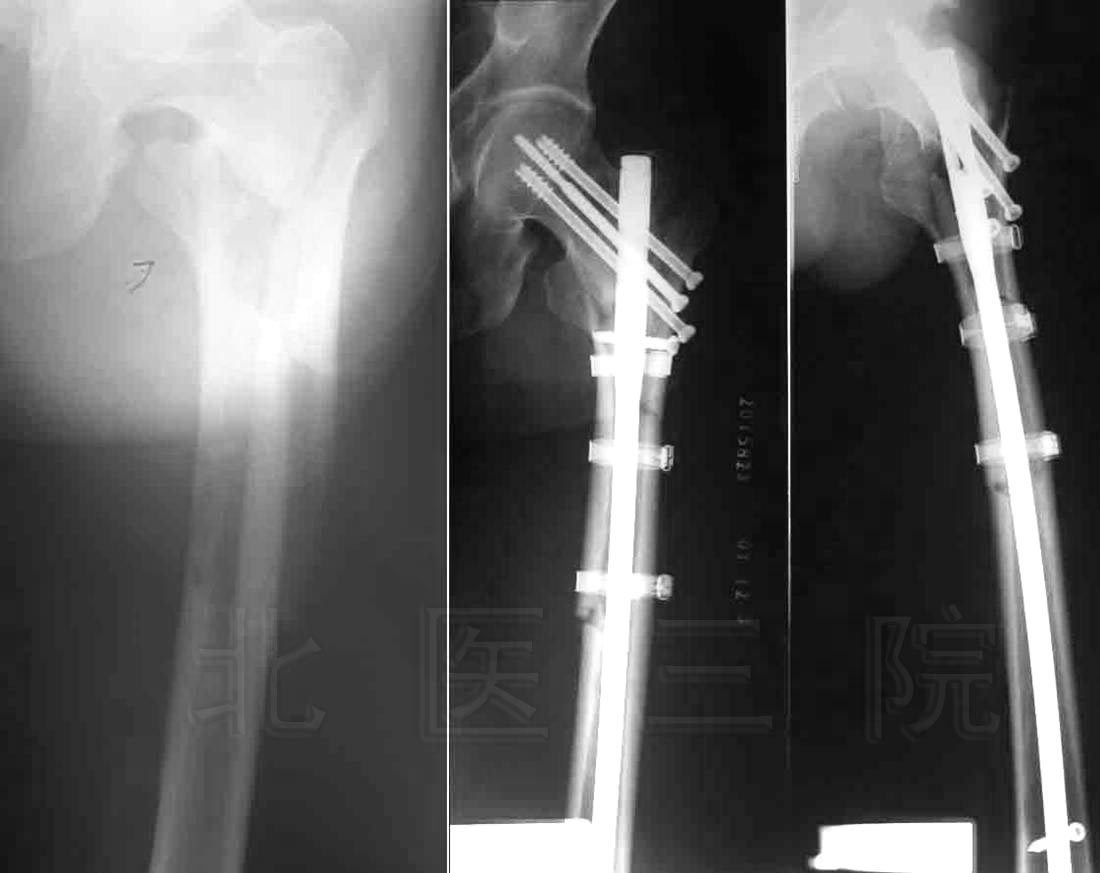

图为:85岁,股骨粗隆部粉碎骨折,微创置入LISS,术后 3个月骨折愈合

85 years old female, completely displaced fracture of proximal

right femur. Fracture healed 3 months after reverse femoral LISS fixation.

1)股骨上端骨折